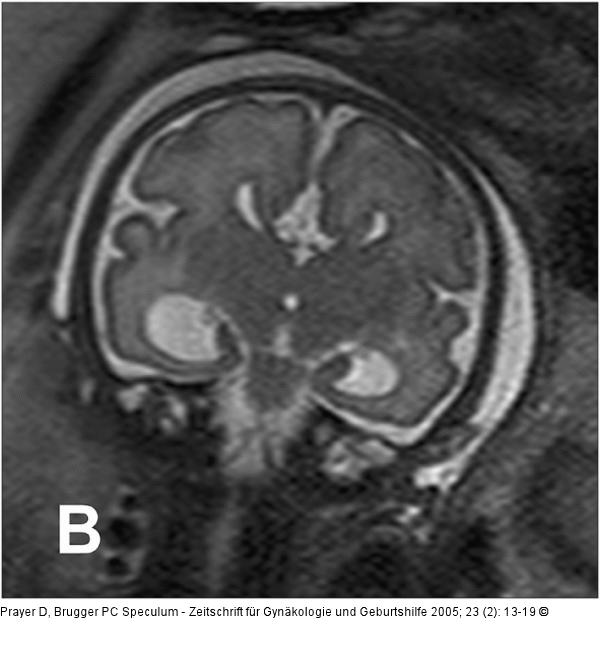

Abbildung 2a-b: Pränatale Magnetresonanztomographie SSW 30, Fetus mit Balkenagenesie, A. Medianes Schnittbild: Fehlender Balken, radiäre Gyrierung an der Medialfläche der Hemisphäre. Der Aquädukt und die Vierhügelplatte unauffällig. Der Hirnstamm zeigt dorsal dünklere Signale als ventral, was der normalen, dort bereits in dieser SSW vorhandenen Myelinisierung entspricht. Im Profil geringe Retrognathie. B. Frontales Schnittbild. Typische Konfiguration der Seitenventrikel, die auf Grund der medial der Vorderhörner erkennbaren Probst’sche Bündel weit auseinander stehen. In den erweiterten Temporalhörnern erkennt man eine nahezu senkrecht stehende Hippocampusformation, was einer Malrotation entspricht. Die Gyrierung ist symmetrisch, eine pathologische Konfiguration des frontalen Anteils des Gyrus cinguli, wie sie im Rahmen der Balkenagenesie zu erwarten ist, besteht. Intrazerebral ist die zelldichtere und daher dünklere Stammganglienregion von der helleren weißen Substanz, die ebenfalls in entwicklungsbedingt unterschiedliche Graustufen gegliedert ist, abgrenzbar. |

SSW 30, Fetus mit Balkenagenesie, A. Medianes Schnittbild: Fehlender Balken, radiäre Gyrierung an der Medialfläche der Hemisphäre. Der Aquädukt und die Vierhügelplatte unauffällig. Der Hirnstamm zeigt dorsal dünklere Signale als ventral, was der normalen, dort bereits in dieser SSW vorhandenen Myelinisierung entspricht. Im Profil geringe Retrognathie. B. Frontales Schnittbild. Typische Konfiguration der Seitenventrikel, die auf Grund der medial der Vorderhörner erkennbaren Probst’sche Bündel weit auseinander stehen. In den erweiterten Temporalhörnern erkennt man eine nahezu senkrecht stehende Hippocampusformation, was einer Malrotation entspricht. Die Gyrierung ist symmetrisch, eine pathologische Konfiguration des frontalen Anteils des Gyrus cinguli, wie sie im Rahmen der Balkenagenesie zu erwarten ist, besteht. Intrazerebral ist die zelldichtere und daher dünklere Stammganglienregion von der helleren weißen Substanz, die ebenfalls in entwicklungsbedingt unterschiedliche Graustufen gegliedert ist, abgrenzbar. |